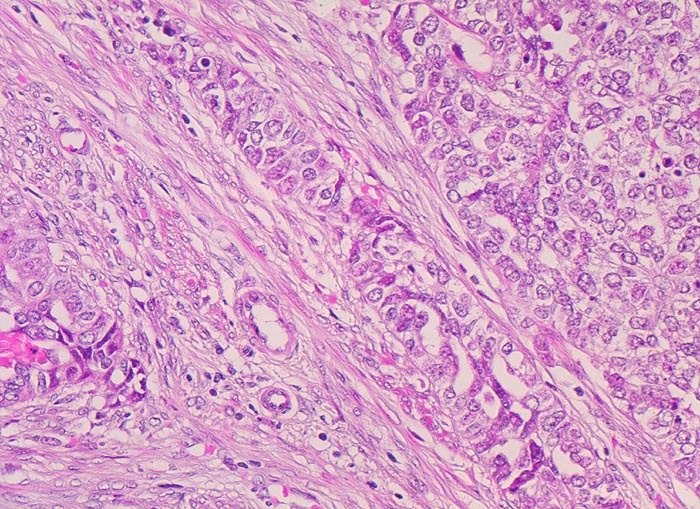

endometrioides Adenokarzinom: Invasion des Myometrium

Solide Tumorzellverbände infiltrieren die glatte Muskulatur des Myometrium. Die Tumorzellen haben grosse runde vesikuläre Kerne und wenig Zytoplasma.

Exophytischer, in das Uteruscavum hineinragender, weicher fokal hämorrhagischer Tumor ausgehend von der Uterushinterwand. Das Tumorgewebe infiltriert die innere Hälfte des Endometriums.

Das pT Stadium und das FIGO Stadium von Karzinomen, die auf den Uterus beschränkt sind, ist abhängig von der myometranen Infiltrationstiefe:

pT1a/FIGO Ia: Tumor auf das Endometrium beschränkt, keine Invasion des Myometrium.

pT1b/FIGO IB: Invasion der inneren Myometriumhälfte.

pT1c/FIGO IC: Invasion der äusseren Myometriumhälfte.

Das Vorliegen eines Stadium pT1c stellt eine Indikation zur Lymphadenektomie dar.